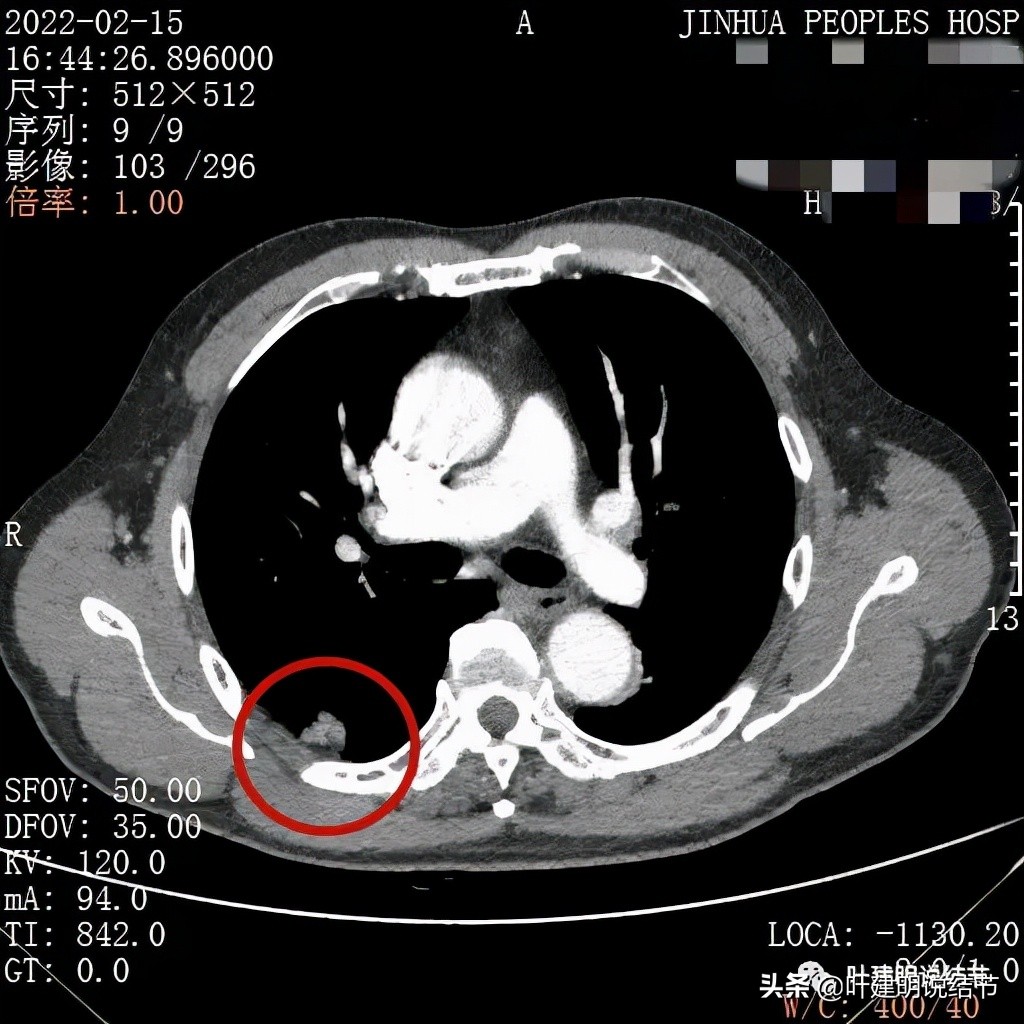

纵隔窗病灶密度不均,有强化,与胸壁之间有低密度间隙

冠状位显示闰灶叶间裂处凹向病灶中心部位以及与胸壁间的界限

矢状位病灶叶间裂受牵拉(蓝色箭头)以及边缘不平膨胀浅分叶征(砖色箭头)

上图是轴位、冠状位与矢状位的图像